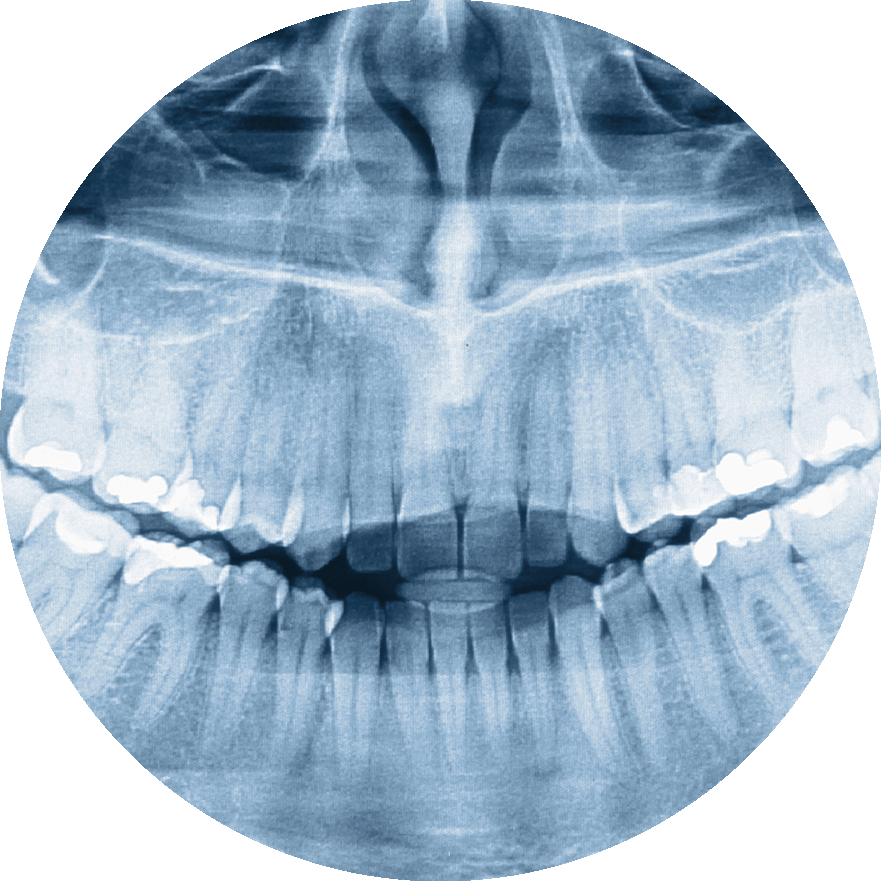

Digital X-rays

Digital X-rays make clear images of your jawbone and teeth to find cavities, gum disease, and other problems with 90% less radiation than traditional film X-rays. Blooming Dental & Implant Center is proud to offer the class-leading DEXIS Titanium Digital X-ray sensor. DEXIS Titanium is the most advanced sensor that produces phenomenal image clarity and has rounded corners for comfort for adults and children.